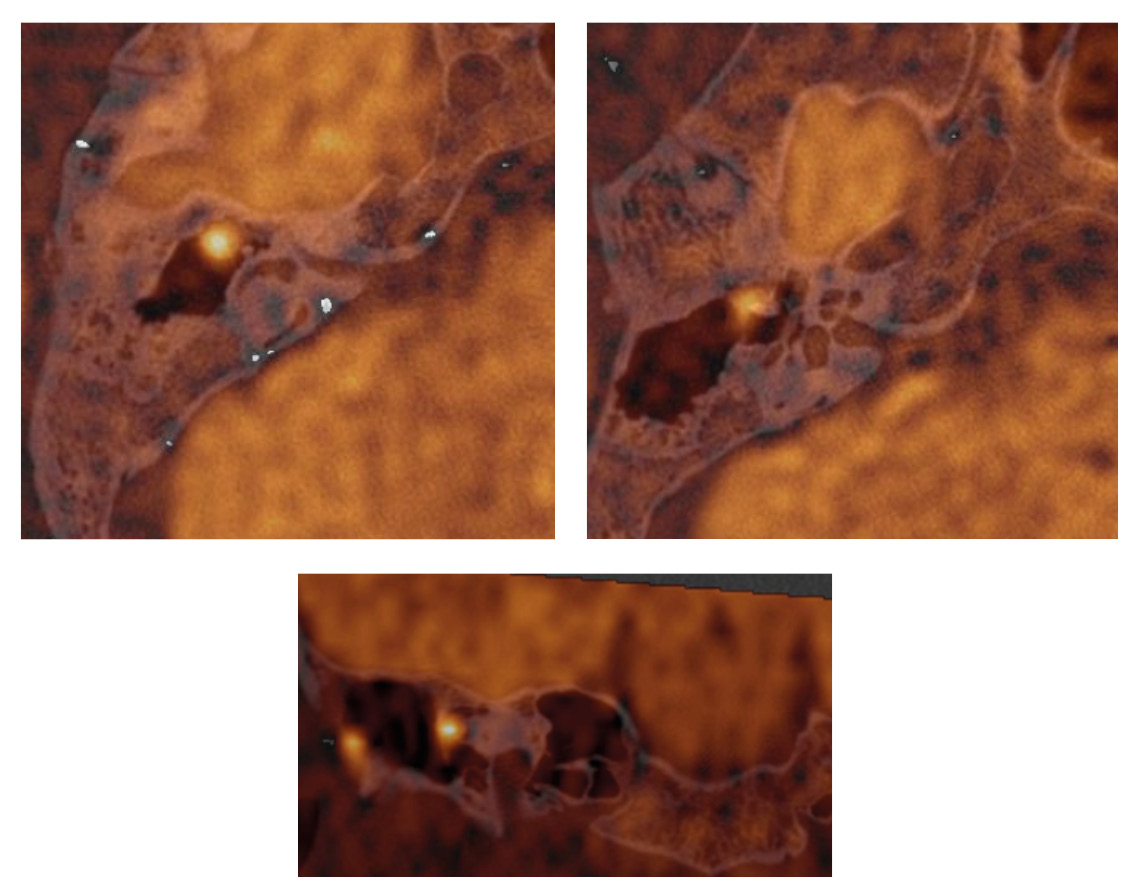

При сравнении сигналов от холестеатомы и очагов ограничения МР-диффузии, обусловленных артефактами или локальным ограниченным воспалительным процессом, в средних значениях сигнал от холестеатомы был ниже, чем от нехолестеатомного процесса (табл. 5). Однако диапазон значений нехолестеатомных процессов, локально ограничивающих МР-диффузию, в том числе включает в себя значение сигнала от холестеатомы, что видно на рис. 7. Поля сигналов от холестеатомы и от не холестеатомы перекрываются в средних значениях.

Таблица 5. Анализ сигналов от холестеатомы и артефактов, мм²/с (Me (LQ; UQ))

Показатель | Локализация | Значение p | Значения р, post-hoc | ||

холестеатома (1) | сигнал от мозга (2) | артефакт (3) | |||

Сигнал | 878,5 (780; 999) | 1020 (932,2; 1113,2) | 1089,5 (718,8; 1405,2) | < 0,001 | 1–2: < 0,001 1–3: < 0,001 2–3: 0,934 |

SD | 63 (44; 83) | 71,5 (52; 90) | 63,5 (40; 91,2) | 0,004 | 1–2: 0,004 1–3: 0,623 2–3: 0,217 |

Рис. 7. Анализ распределений стандартизованной разности сигналов (стандартизованный сигнал с учетом отклонения)